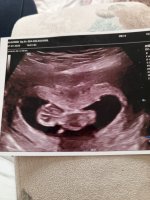

10 hafta 6 günlük bebişim 3 oğlum var tabiki önceliğim sağlıklı olması anlayan varmı çok merak ettım doktor soylemedı şimdiden tşk ederim cevap veren olursa 🥰🥰

Ben kendi bebeğimin cinsiyetini nub teorisine göre tahmin etmiştim ama sizinki çok minik 🥰 2 hafta sonra olsaydı belki anlaşılırdı. Şu görünen kemik düz olduğunda kız, yukarı doğru eğik olduğunda erkek diyorlar